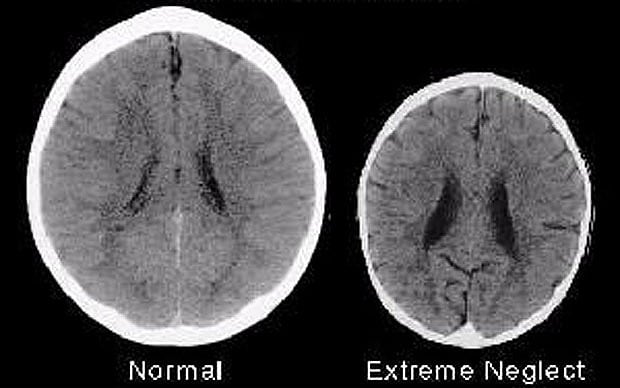

Tấm phim chụp lại bộ não của 2 trẻ em đã được các nhà nghiên cứu phân tích. Nếu nhìn nhận dưới góc độ không chuyên môn, ta chỉ nhìn thấy sự khác biệt đơn giản về kích thước giữa 2 bộ não. Tuy nhiên, các nhà thần kinh học cho rằng, sự khác biệt này sẽ dẫn đến sự phát triển khả năng của bé về sau.

Cụ thể hơn, dưới đây là não của 2 đứa trẻ 3 tuổi. Chỉ cần thoáng quan sát, ai cũng nhận ra bộ não bên trái lớn hơn rất nhiều, đúng không?

Tấm phim chụp này đã được nhiều nhà thần kinh học sử dụng để nghiên cứu. Theo đó, bộ não bên phải thiếu đi rất nhiều khu vực cơ bản, và sự thiếu hụt này có thể gây ảnh hưởng nghiêm trọng đến sự phát triển của trẻ sau này.

Đứa trẻ thiếu may mắn khi trưởng thành sẽ kém thông minh hơn, khả năng đồng cảm thấp hơn, có xu hướng sử dụng chất kích thích nhiều hơn, và thiên hướng bạo lực cũng gia tăng. Bé cũng dễ trở thành đối tượng thất nghiệp, phải sống nhờ trợ cấp xã hội, đồng thời phải gánh chịu tương lai chứa nhiều bệnh tật phía trước.

Rất tiếc là không phải! Các chuyên gia cho biết, lý do làm nên sự khác biệt này đến từ các bà mẹ, mà cụ thể là cách chăm sóc của mẹ với bé. Đứa trẻ bên trái nhận được đầy đủ sự yêu thương, chăm sóc và trách nhiệm, trong khi đứa trẻ thiếu may mắn kia sống trong bạo hành và gần như bị bỏ bê hoàn toàn.